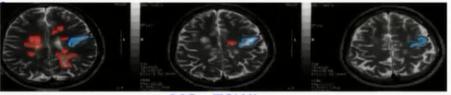

常规影像技术与SVD诊断见下图。

(1)陈旧性脑梗死

FLAIR影像结果显示,中间是低信号,周围是高信号。据此进行鉴别诊断。

(2)急性腔梗、扩大的脑血管周围间隙鉴别

红色箭头:急性腔梗, DWI:高信号;T 2高信号;T 1:低信号;

蓝色箭头:扩大的血管周围间隙, DWI:低信号;T 2高信号, 接近脑脊液的信号;T1:低信号,周围没有增生的胶质细胞。

(3)陈旧性脑出血鉴别诊断

T2WI高信号伴周围低信号环(含铁血黄素沉积)。